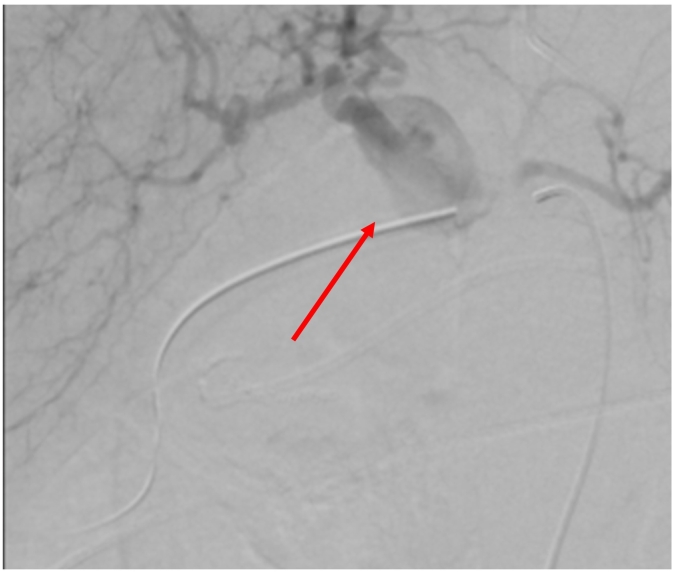

Due to the persistence of melaena and rectal bleeding associated with new upper gastrointestinal bleeding, a new EGDE was requested with evidence of active layered bleeding in gastric ulcers. Hemostasis was performed with hemoclip. Selective arteriography was performed, where an abrupt interruption of the gastroduodenal artery was found in relation to the pancreatic mass confirming a pseudoaneurysm (Fig. 2). As well, initial suspicion of rupture of the pseudoaneurysm into the duodenum was ruled out according to the arteriography, and for that reason the preferred management was an endovascular coil embolization, which was performed, achieving distal occlusion of the vessel, with no evidence of persisting bleeding on inspection (Fig. 3).

Fig. 2.

Endovascular view of gastroduodenal artery pseudoaneurysm (red arrow pointing to the pseudoaneurysm).